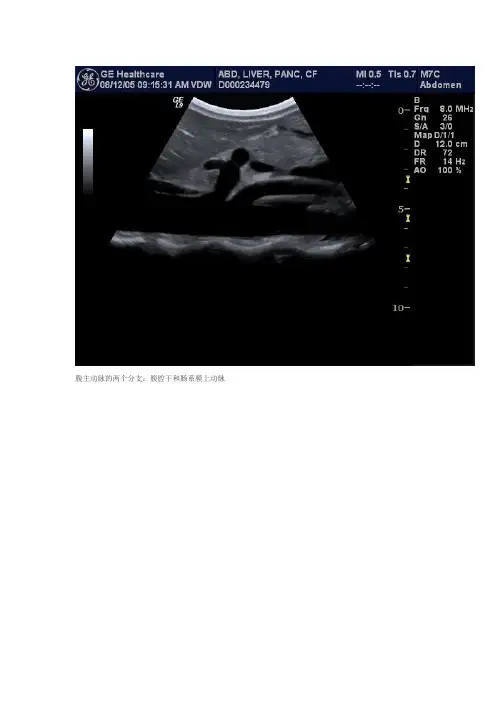

腹主动脉的两个分支:腹腔干和肠系膜上动脉